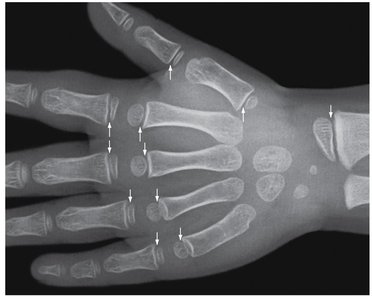

Short Bones: Boxy, found in wrists (carpals) and ankles (tarsals).

Long Bones: Long and slender (e.g., humerus, femur, fingers, toes).

Sesamoid Bones: Small, round, flat bones within tendons (e.g., patella).

Interstitial Growth: Growth in length at epiphyseal plate; ends with epiphyseal closure (epiphyseal line remains).